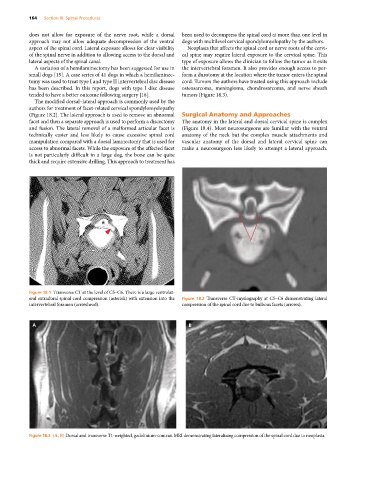

Figure 18.1 Transverse CT at the level of C5–C6. There is a large ventrolat-

eral extradural spinal cord compression (asterisk) with extension into the Figure 18.2 Transverse CT‐myelography at C5–C6 demonstrating lateral

intervertebral foramen (arrowhead). compression of the spinal cord due to bulbous facets (arrows).

Figure 18.3 (A, B) Dorsal and transverse T1‐weighted, gadolinium‐contrast MRI demonstrating lateralizing compression of the spinal cord due to neoplasia.